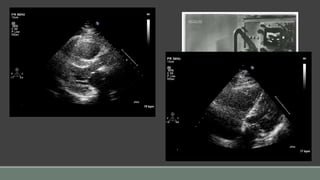

3D live: Thin slice mode

3D live: Zoom mode

3D Imaging: Biplane view